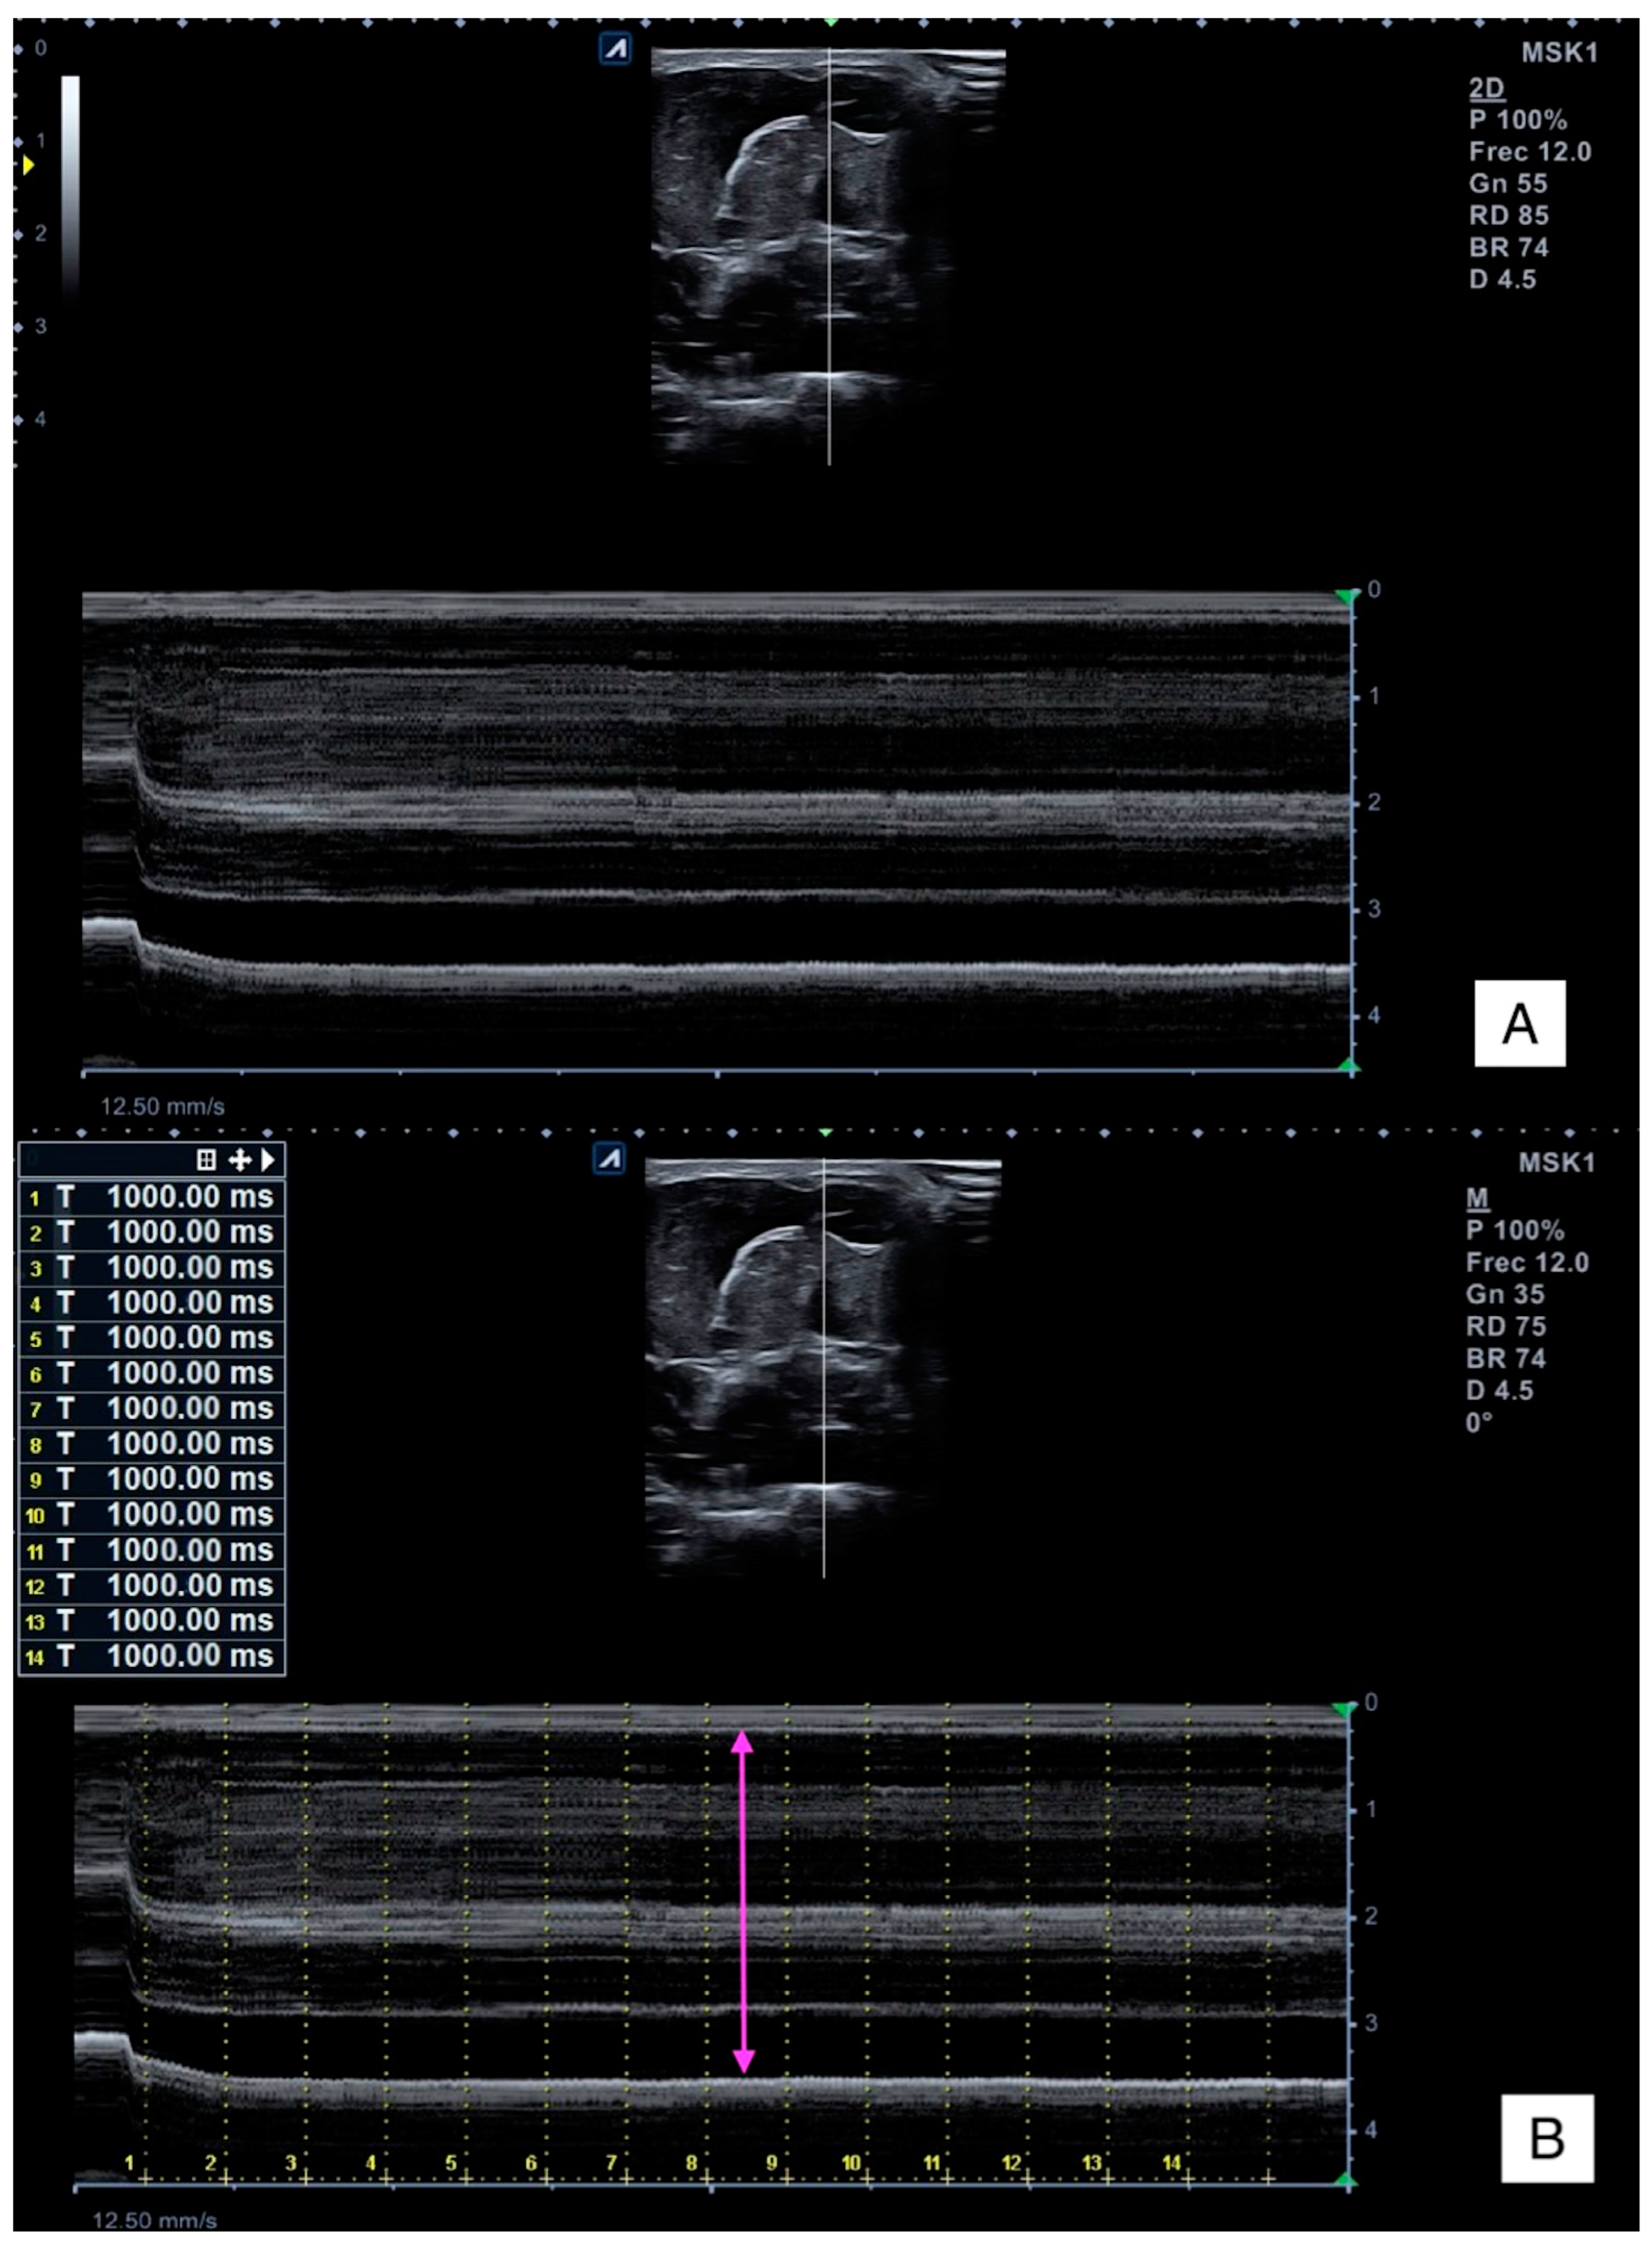

2.4.1. Ultrasound Imaging

2.5.2. Muscle Thickness Change